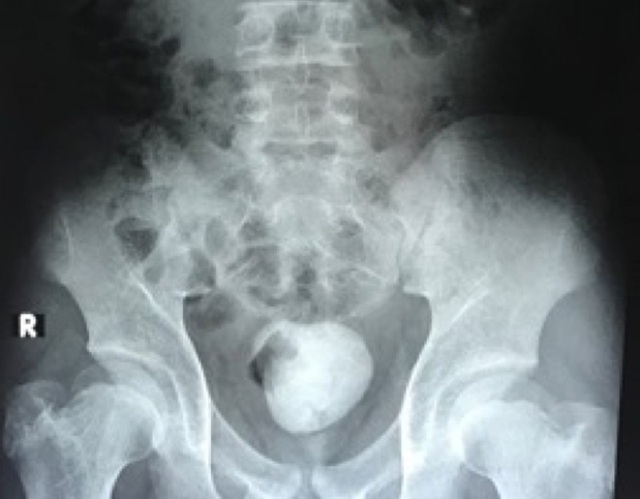

Viên sỏi khổng lồ nằm trong ổ bụng bệnh nhi

Các xét nghiệm và kết quả khảo sát hình ảnh cho thấy bệnh nhi bị sỏi bàng quang tái phát với kích thước lớn khoảng 10cm. Đây là nguyên nhân khiến cậu bé tiểu khó, tiểu đau, thậm chí gây bí tiểu do sỏi che lấp cổ bàng quang và niệu đạo nên nước tiểu không thoát ra ngoài được. Nước tiểu ứ đọng trong bàng quang tạo điều kiện cho vi trùng phát triển gây nên tình trạng nhiễm trùng đường tiểu.